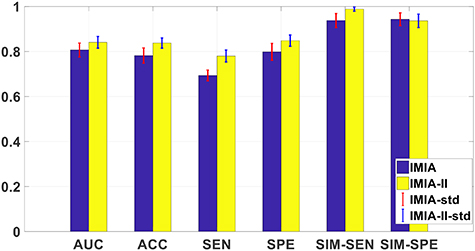

This experiment is to compare the model performance after optimizing through IMIA and IMIA-II, and the results are shown in figure 8. Compared with IMIA, the model trained by IMIA-II can obtain better performance, which shows that our newly defined probability-based objective function can get a more reliable model. Specifically, IMIA-II can obtain higher AUC and SIM-SEN, which suggests that the model trained by IMIA-II is more reliable.

Figure 8. The reliability evaluation results for IMIA and IMIA-II.

Download figure: